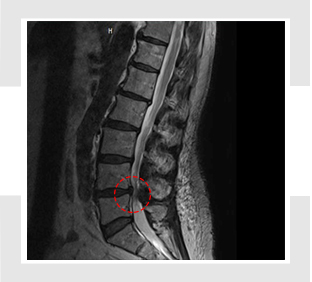

허리 디스크와는차이나게 척추관 협착증은 요통보다는 다리 저림이나 당김 증상이 있어, 보행에 제일 큰 고충을 체감할 수 있습니다. 때문에 오래 걷기가 힘들고 오래 걷지 않았음에도 자꾸 주저앉게 되는 성향이 존재하는데 표준적인 협착증의 증상이라 할 수 있습니다. 기본적으로 요추부(허리)의 문제이긴 하지만 허리디스크와 다르게 허리 통증이 한결같이 동반되지는 않으며, 있더라도 허리디스크에 대조해서 적은 정도의 통증이 일어납니다.

신경을 누를 때 신경의 지배를 받는 부위로 쑤시거나 화끈거리는 통증을 호소하게 되겠습니다. 만에 하나라도 경추부(목)에 척추관 협착증이 만들어 낸다면 상/하지 모두에 영향을 줄 수 있어 다리 근력감소, 보행 불편을 나타나게 할 수 있습니다. 요추(허리) 협착증은 방사통이 엉덩이에서 시작, 다리 아래로 하향할 수 있고 이 증상을 거의 좌골신경통이라 합니다.

척추관 협착증은 척추관의 좁아짐과 신경 구조에 압력이 가해지는 것으로 인해 많은 종류의 증상이 일어날 수 있어요. 주로 통증이 띄엄띄엄 생겨날며 허리, 목, 아니면 다리 등의 부위에서 통증이 나타날수 있습니다. 뿐 와 함께 또 저림 혹은 마비가 나타날수 있기도하고 특이하게다리에서의 저림이나 마비가 예사로 보여집니다.

또한 척추관 압력으로 인해 근육 약화가 발생하여 근력이 약해지는 경우도 있다고 합니다.

이로 인해 일상적인 움직임이나 운동에 괴로움을 겪어볼 수 있어요. 척추관 협착증으로 인해 척추 구조가 변형되었다거나 신경 구조에 압력이 적용되면 동작의 제한이 등장하고 허리 부위의 증상이 다리로 통증이 방사될 수도 있고요.

신경 압박이 안좋아지면, 신경을 통한 감각 전파이 순조롭지 않아 통증과 아울러 감각 저하, 이상감각을 호소할 수 있습니다. 경추 협착증의 경우, 감각 저하가 상 / 하지 모두 일어날 수 있습니다. 신경이 견딜 수 있는 수준 마지막으로 압력이 증가하면, 하지에 근력이 감량하게 되겠습니다.

심하다 못해 나중에는 족하수, 즉 발에 힘이 안입회하고 걸을 때 발이 끌리는 현상이 생기게 되겠습니다. 허리를 앞으로 숙이면, 척추관이 넓어지고 해서 허리를 숙이고 있거나 앉아있는 것이 소홀하게 느껴지고요. 허리를 펴고 오래 걷거나 서있기 어려우며 100~200m 이상 걸으면 다리에 힘이 빠지거나 통증이 심해 쪼그려 앉아서 쉬게 되겠습니다.